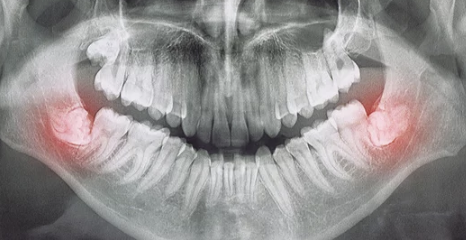

매복 사랑니는 턱뼈 안에서 완전히 나오지 못하거나 비정상적인 각도로 자란 사랑니를 말합니다. 이런 사랑니는 주변 치아를 밀거나 잇몸 염증, 통증 등을 유발할 수 있어 발치가 필요합니다.

- X-ray 검사: 매복 상태 확인.

- 발치 수술: 잇몸과 뼈 일부를 제거한 후 사랑니를 발치.